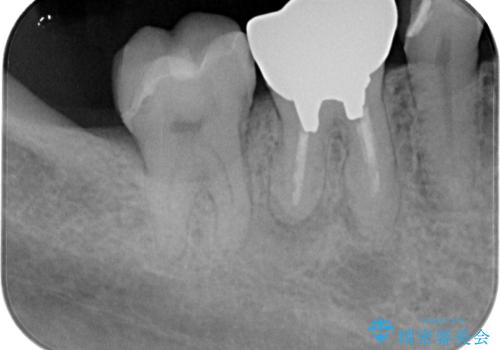

- 適合の良くない銀の詰め物が入っており、白い詰め物へのやり替えをご希望された患者様です。

メタルインレーを除去したところ、虫歯ができていたため取り除いたうえでハイブリッドインレー修復を行いました。

インレーセット時には唾液の侵入を防ぐためにラバーダム防湿を行っています。

Ⅲ級咬合の患者さまで、奥歯への負荷が強いため、セラミックよりも破損のリスクが低いハイブリッドインレー治療を行いました。